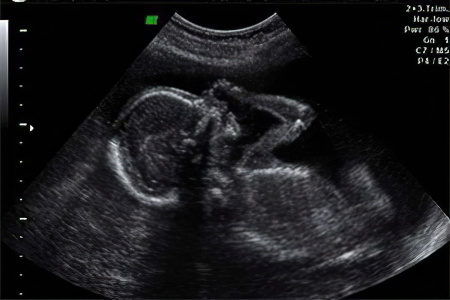

УЗИ

Второе плановое ультразвуковое исследование обычно проводится с 20 по 24 недели беременности. Однако в некоторых случаях, исходя из медицинских показаний, его могут назначить на 1-2 недели раньше. Основная задача этого исследования — оценка развития плода, состояния плаценты и матки. Если есть подозрения на генетические или хромосомные аномалии, специалист анализирует размер носового хряща и параметры воротниковой зоны плода.

Во время УЗИ можно выяснить:

• Состояние миометрия (мышечного слоя матки);

• Положение плаценты и риск предлежания;

• Состояние и объем амниотической жидкости;

• Соотношение размеров матки и плода;

• Оценка состояния внутренних органов и сердцебиения ребенка;

• Пол будущего малыша.

У плода уже формируется режим сна и бодрствования, поэтому во время исследования можно увидеть его в состоянии покоя или активно двигающимся в околоплодных водах.